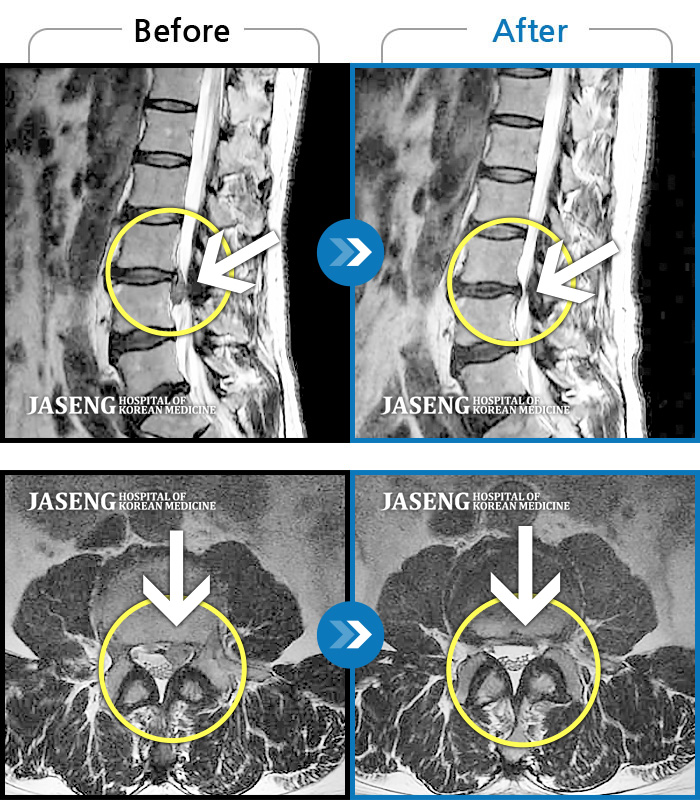

허리디스크

잠실 · 한상욱 원장

우측 엉치부터 우측 다리부터 발끝까지 저리고 아프다. 감각까지 먹먹하다.

촬영시기

2022.04.15 ~ 2022.10.22

2022.12.02